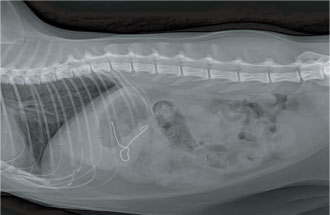

자두씨 이물 섭취

치료 후 (자두씨 제거 모습)

방사선 검사 (철사 이물 확인)

위 내시경 치료 모습